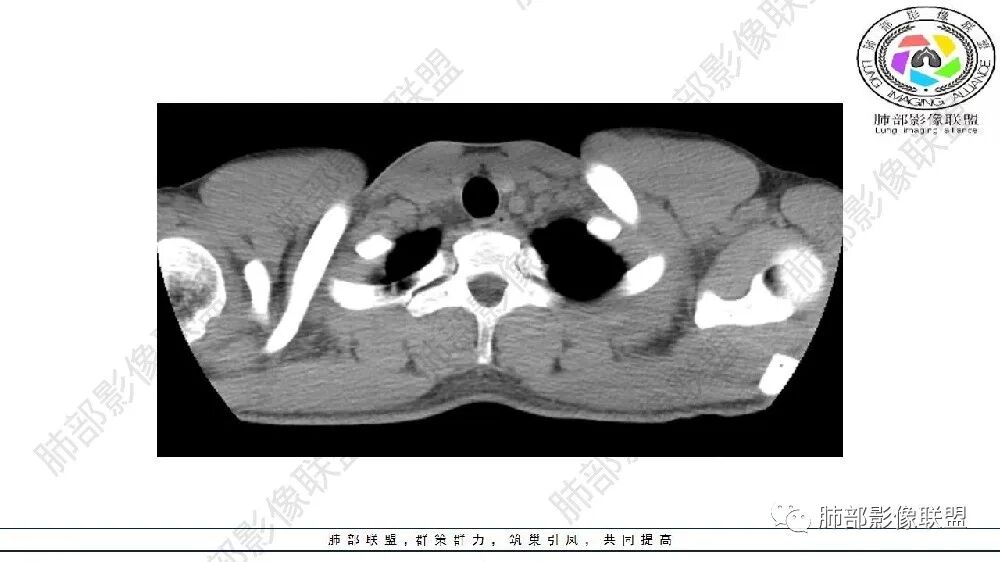

异常动脉大多为1~3支,多来自降主动脉,亦有来自腹主动脉。少数叶外型可来自肺动脉、肋间动脉或腹腔动脉。

五、诊断

X线检查是最早的诊断线索。胸部CT血管重建尤其是MSCT可清楚显示异常的体循环血管的供血,以及血管起始部位、分支和走行,是诊断PS的可靠手段。血管造影术曾经是诊断PS的金标准,但其侵人性操作限制了其在临床上广泛应用。目前常将胸部CT血管重建用于PS的诊断,可显示1支或多支异常供血动脉,诊断准确率达100%,尤其是增强MSCT不仅可检出细小动脉,更能提供异常动脉来源与走行的详细血管路线图,可以帮助完善术前评价,结合其简便、易行、无创的特点,可作为PS确诊首选。磁共振血管成像(MRA)也可以显示异常血管的供血。MRI和MRA对碘剂过敏者是较好的选择。产前超声是诊断PS的首选方法,MRI可直接显示胎儿隔离肺的位置和形态,并确定其供血血管,对于胎儿PS的诊断具有较高价值,可作为产前胎儿超声检查的重要补充。文献显示产前超声诊断的12例胎儿PS,超声诊断符合率83.3%,误诊2例(1例为隔疝,1例为肺囊腺瘤);产前MRI检查诊断准确率为91.7%,误诊1例(隔离肺误诊为腹腔肿瘤)。16例BPS患儿中,15例患儿的产前MRI检查结果与出生后诊断结果一致,其中,叶内型10例,叶外型5例;1例产前MRI诊断为右肺下叶BPS,出生后手术病理检查证实为先天性肺囊腺瘤样畸形(congenital cystic adenomatiod mal- formation,CCAM),产前MRI诊断BPS的准确率为15/16。